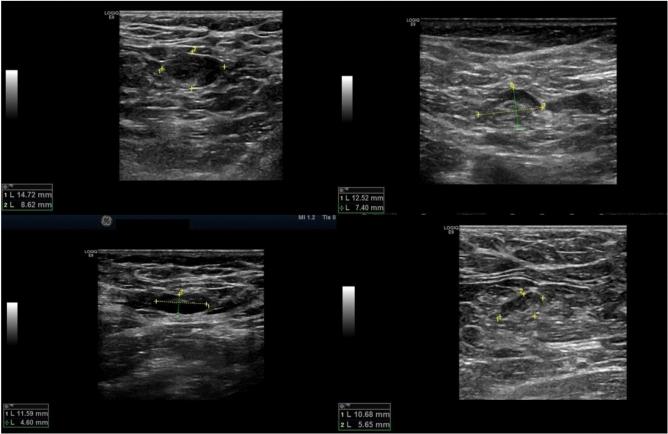

For breast cancer patients with physical exam node negative but radiological finding node abnormal (cN0/rNa), the NCCN and ASCO guidelines recommend sentinel lymph node biopsy (SLNB) as the first-line axillary staging. However, patients who undergo surgery firstly may be upstaged to pathological II-III status, and these patients happen to be the adaptive population of neoadjuvant therapy (NAT). There is no consensus on the optimal management of cN0/rNa patients. The aim is to explore the optimal management strategy of these patients. We performed a retrospective real-world study of 1414 cN0/rNa patients from June 2014 to October 2022. There were 1003 patients underwent surgery first and 411 patients underwent surgery after NAT. We analyzed the real-world conditions of these patients, compared axilla tumor burden between these two groups. In addition, we compared benefit ratio of axillary surgery and regional nodal irradiation (RNI) de-escalation under the two strategies. Among 1003 patients underwent surgery first, the positive and negative rates of fine needle aspiration (FNA) were 18.5% and 81.5%, respectively. There were 66.1% had ≤ 2 lymph nodes+. There were 40.8% of FNA+ patients could be exempted from ALND underwent surgery first. In 411 patients underwent surgery after NAT, the FNA positive and negative rates were 60.8% and 49.2%, respectively. There were 54.4% of FNA+ patients achieved axilla pathologic complete response (apCR) and could omit ALND after NAT. The apCR was 67.3% in HER2+/TNBC subtypes. According to the NSABP-B51 trial, there were 0 and 54.4% of FNA+ patients could omit RNI among surgery first and after NAT, respectively. Among 1-2 sentinel lymph node (SLN)-positive patients underwent surgery first, with a median follow-up 49 months, there was no difference of survival benefit between SLNB-only and SLNB-ALND. Compared with 1-2 SLN+ patients without RNI, RNI could bring better invasive disease-free survival (97.38% vs. 89.36%, P = 0.046) and breast cancer special survival (100% vs. 94.68%, P = 0.020). It is safe to perform SLNB omitting ALND when detected 1-2 positive SLNs in cN0/rNa patients. Patients with HER2+/TNBC subtypes underwent surgery after NAT had more chance to benefit from dual de-escalation, including axillary surgery and RNI de-escalation.